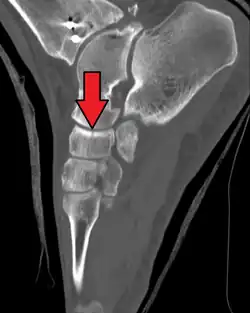

The human navicular is not a commonly broken bone but it breaks due to two reasons. The first mechanism is a stress fracture which happens commonly in athletes,[7] and the other mechanism is a high energy trauma.

The navicular bone is a keystone of the foot: it is part of the coxa pedis and articulates with the talus, first, second and third cuneiform, cuboid and calcaneus. It plays an important role in the biomechanics of the foot, helping in inversion, eversion, and motion; it is a structural link between midfoot and forefoot and it is part of the longitudinal and transverse arch of the foot.